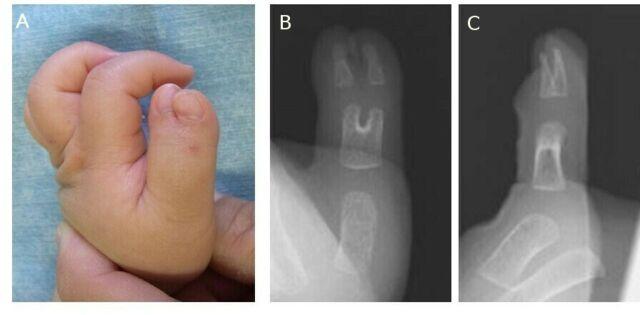

We present a case of a postoperative cartilage defect in a patient with polydactyly who was treated with a costal osteochondral graft. Excision of the radial digit and ligamentous periosteal flap with longitudinal osteotomy were performed when the patient was 1 year old. The alignment of the interphalangeal joint was straight after surgery, but the deviation gradually developed. A revision surgery using a costal osteochondral graft was performed when the patient was 3 years old. A satisfactory outcome was obtained at the 3-year follow-up. The authors suggest that a costal osteochondral graft may be a reasonable option for revision surgery for a postoperative cartilage defect.

我们报告了 1 例多指术后软骨缺损患者的病例,该患者接受了肋软骨骨软骨移植治疗。当患者 1 岁时,进行了桡侧指切除和韧带骨膜瓣的纵向骨切开术。术后指间关节对线笔直,但逐渐出现偏斜。当患者 3 岁时,进行了使用肋软骨骨软骨移植的翻修手术。3 年随访时获得了满意的结果。作者认为,肋软骨骨软骨移植可能是术后软骨缺损翻修手术的合理选择。